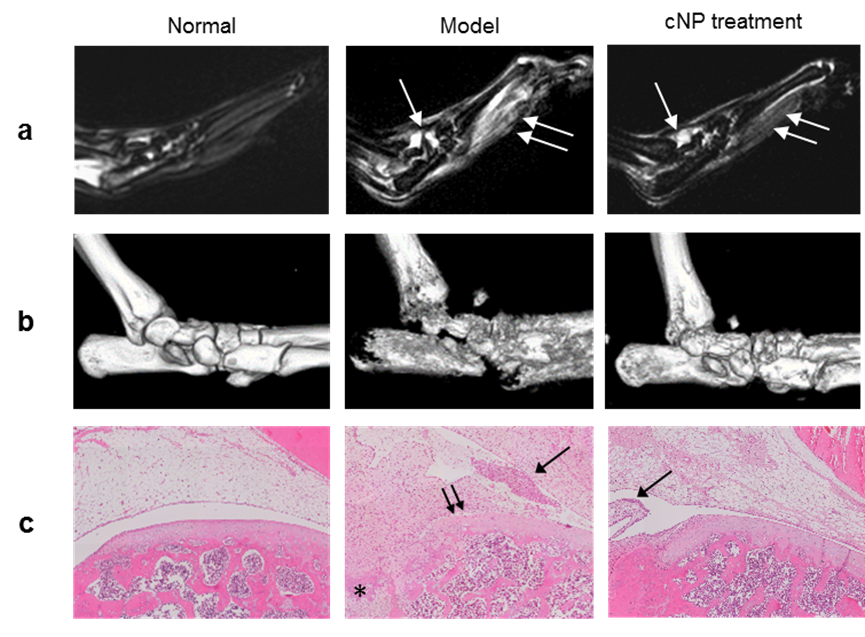

图2. cNP治疗后大鼠模型的软组织(a. 后掌MRI影像)、骨质量(b. 踝关节microCT影像)和炎症浸润改善(c. HE染色)的结果。

我院功能生物医用材料团队利用阳离子聚合物材料结合游离核酸,发现聚合物材料可以抑制患者自身游离核酸引起的原代细胞炎症反应,观察到纳米材料可以通过炎症导致的高血管通透性富集到动物模型关节部位,从而显著抑制关节的肿胀、骨和软骨的破坏,并且恢复动物活动能力。研究发现,阳离子聚合物纳米粒子cNP与cfDNA的结合能力强,能很好地抑制cfDNA对免疫细胞TLR9的激活,能有效抑制cfDNA引起的RA病人关节积液单核细胞及滑膜样细胞的炎症反应。对慢性大鼠关节炎模型进行静脉注射cNP以后,其关节中的积液及软组织的水肿显著减少,关节骨质破坏程度降低,关节滑膜处的炎症细胞浸润变少,说明cNP对于类风湿性关节炎有明显的疗效。治疗后模型大鼠的行动力得以恢复,表明cNP还能有效解决RA后期面临的关节僵硬而行动不便的问题。